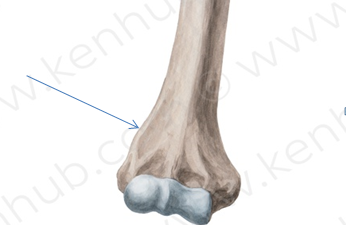

41. This part of humerus is called:

Explanation

The correct answer is the lateral supracondylar ridge. The humerus is a bone in the upper arm, and it has various bony landmarks. The lateral supracondylar ridge is a prominent ridge located on the lateral aspect of the humerus, just above the condyles. It serves as an attachment site for muscles and ligaments, providing stability and support to the elbow joint.

This part of humerus is called: